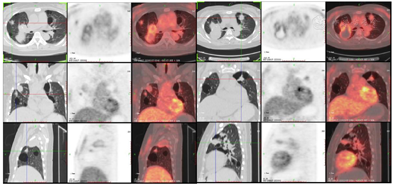

⑤24小时尿蛋白定量0.071g/天,血清免疫固定电泳、尿液游离轻链测定未见明显异常,尿本周蛋白定性阴性。PET/CT示右肺中叶切除术后,右肺上叶尖段、后段囊实密度影,双肺多发薄壁囊肿,双肺多发结节影伴FDG摄取增高,符合轻链沉着症(图4)。